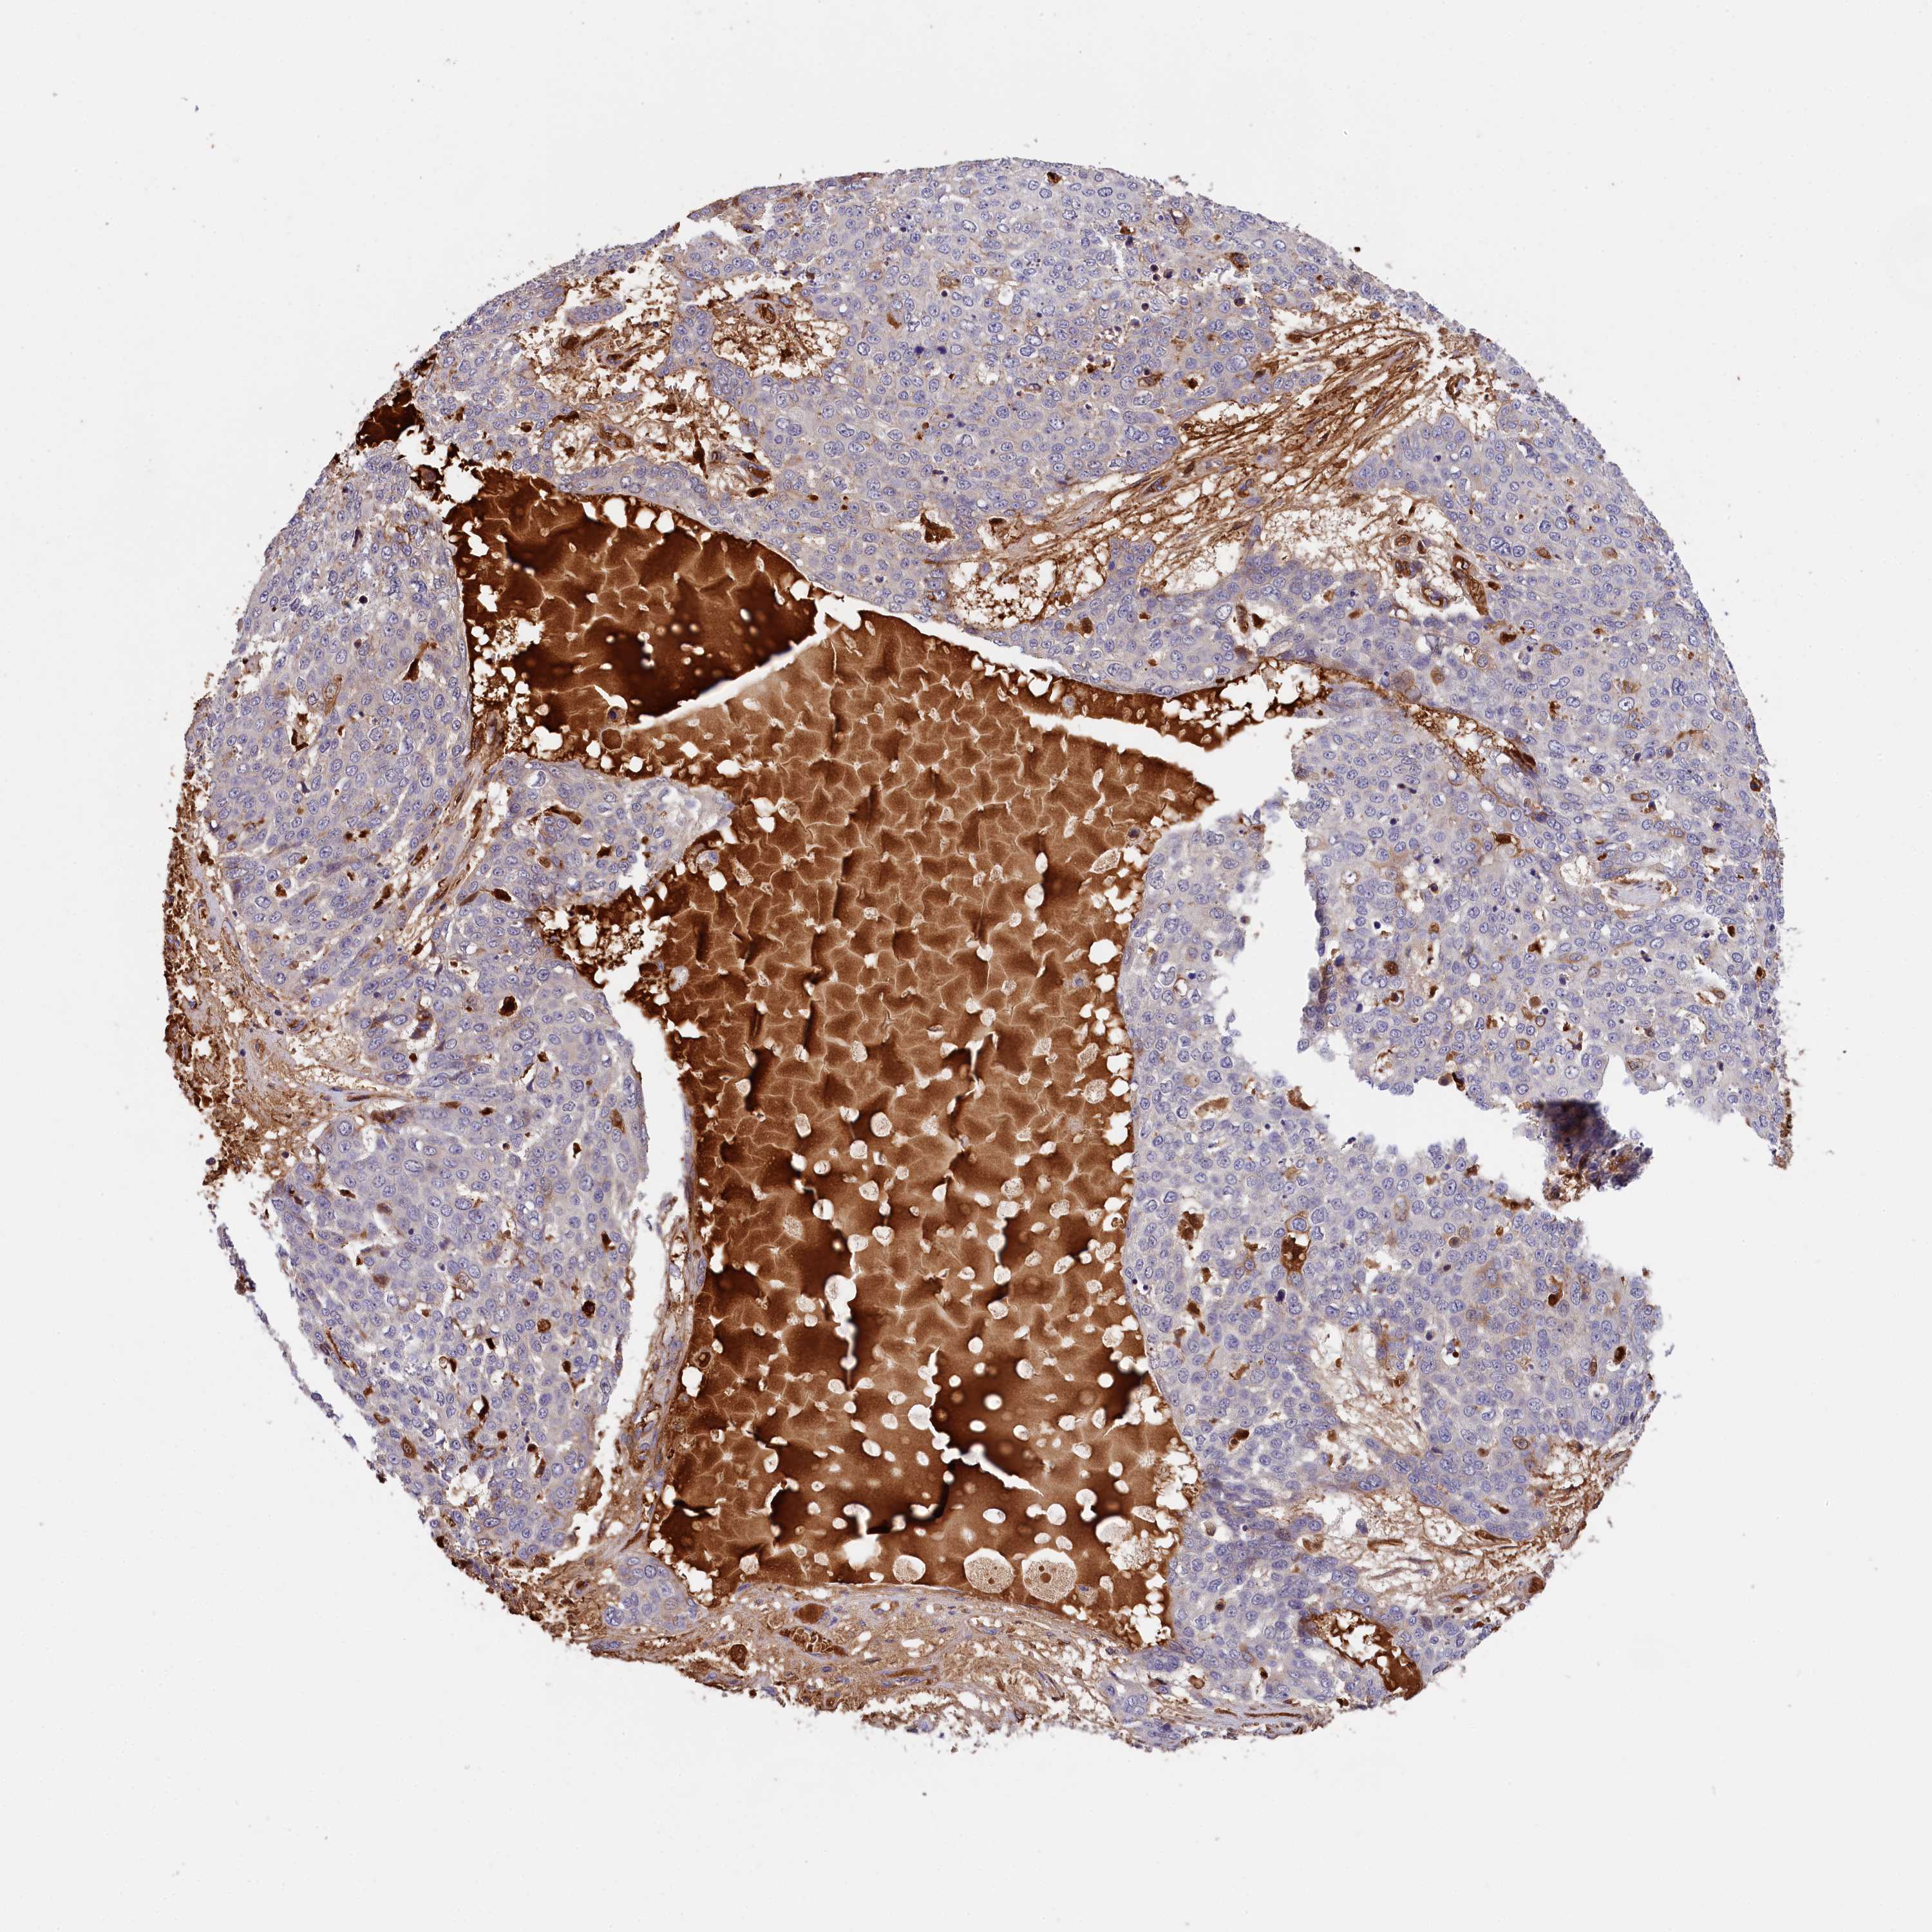

SKIN CANCER - Protein expressioni

A mouse-over function shows sample information and annotation data. Click on an image to view it in a full screen mode. Samples can be filtered based on level of antibody staining by selecting one or several of the following categories: high, medium, low and not detected. The assay and annotation is described here.

Antibody stainingi

Antibody staining in the annotated cell types in the current human tissue is reported as not detected, low, medium, or high, based on conventional immunohistochemistry profiling in selected tissues. This score is based on the combination of the staining intensity and fraction of stained cells.

Each image is clickable and will lead to virtual microscopy that enables deeper exploration of all samples and also displays staining intensity scores, fraction scores and subcellular localization as well as patient and tissue information for each sample.

Antibody HPA041131

Antibody HPA041214

Basal cell carcinoma

Squamous cell carcinoma, NOS

Squamous cell carcinoma, metastatic, NOS